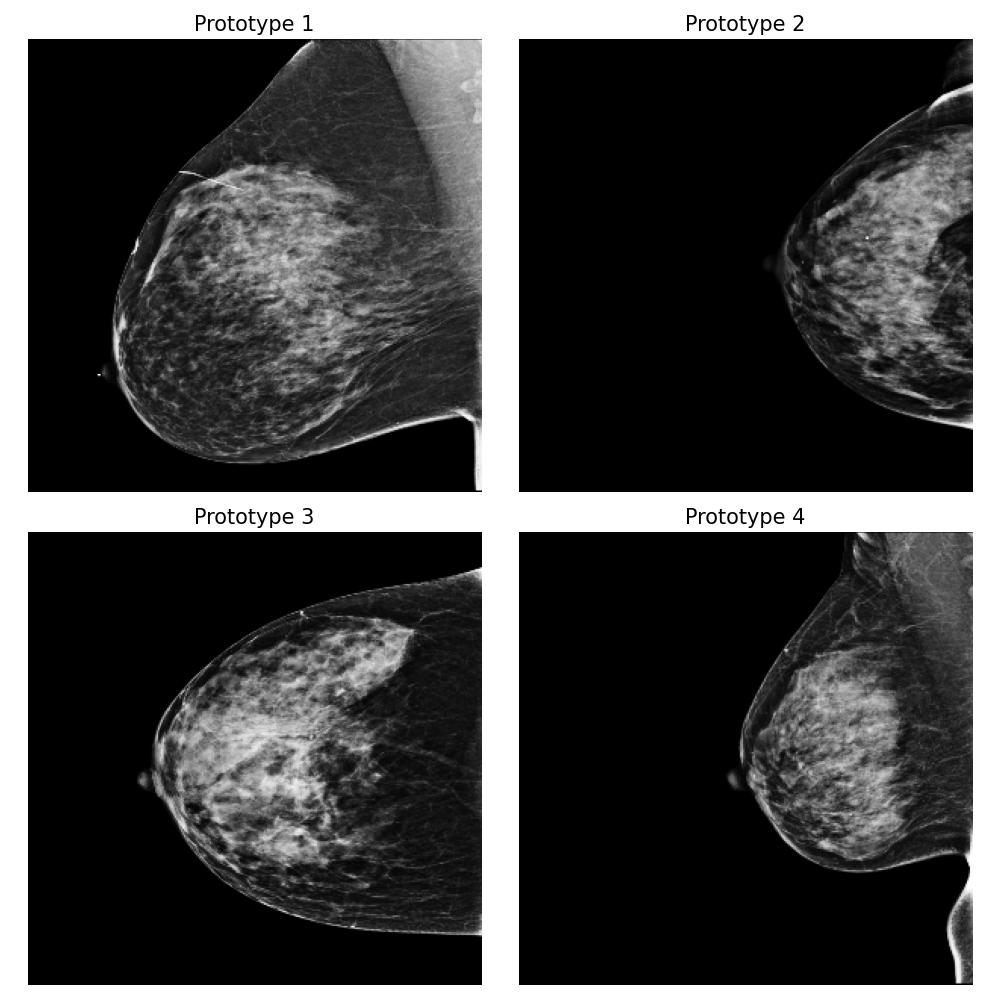

Dataset and

We use the publicly available EMBED dataset (Jeong et al., 2023). To simulate premenopausal and postmenopausal patient populations, we construct two datasets, and , by randomly sub-sampling from EMBED. Dataset comprises 27,224 mammograms from 8,456 patients with dense breast tissue (density category three in EMBED) and 21,675 mammograms from 7,841 patients in density category two. Dataset includes 27,224 mammograms from 2,715 patients with less dense tissue (density category one) and 21,675 mammograms from 7,797 patients in density category two (medium density). All mammograms were preprocessed to remove clinical markers and aligned such that the breast tissue faces left.

For this task, we implemented the “Prototype-summarization-based explanations” described in Section 3.5. We trained a binary vs classifier using the VGG19 feature extractor as backbone and learn four prototypes for each dataset. 97798 mammograms were used for training, and 24450 mammograms were used for testing.

Result

By examining the summarization prototypes shown in Figure 22, we identified tissue density as the primary difference between and . In mammograms, brighter areas correspond to denser tissue. Additionally, we observed that less dense tissue is often associated with larger tissue size. Without our proposed method, human users would need to manually analyze the dataset, which is a labor-intensive and time-consuming task, to reach the same conclusions.

Robustness of the explanation

To examine the robustness of our explanation result, we repeat the explanation algorithm approach on bootstrapped versions of and . Five bootstrapped datasets were constructed by resampling by patients with replacement. As shown in Figure 35 in Appendix Section B.5, we reach the same conclusion for all the bootstrapped datasets.

Coverage evaluation

We again evaluate the coverage quality of the learned set of prototypes using the AUCC score. The coverage curve is shown in Figure 24. We also display the learned latent space for and in Figure 24 and the two datasets and the prototypes are well separated even though they contain overlapping mammograms with density category two (i.e. medium density breasts).